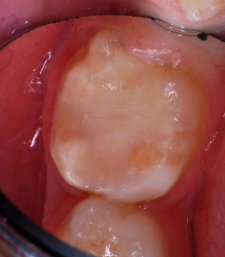

Images of the repaired molar immediately after restoration

Figure 4

13 months postoperatively

Figure 5